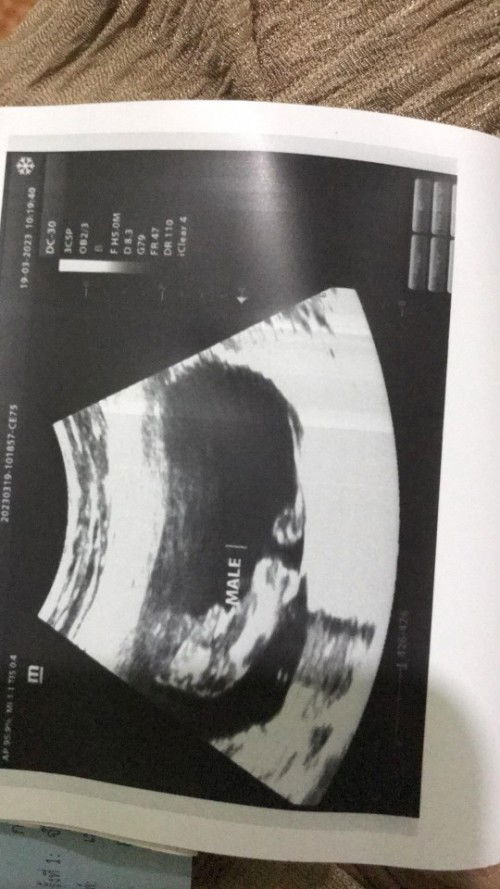

มาแชร์กันค่ะ ท้อง 15W คุณแม่แต่ละบ้าน นน. เท่าให่ ลูกน้อยของแต่ละบ้านนน. เท่าใหร่กันแล้วค่ะ บ้านนี้ อัพเดทวันนี้ 147 g จร้า บ้านนี้ลูกชายจร้า